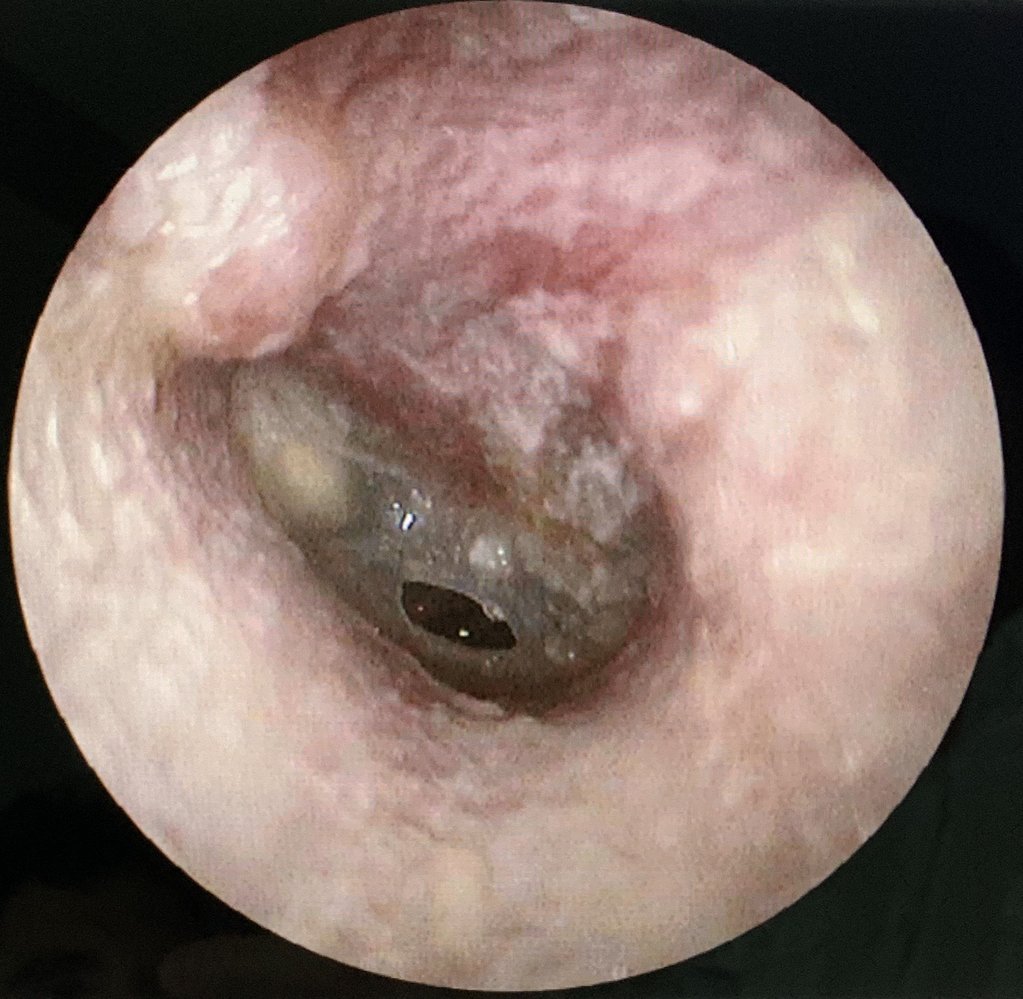

Blast-induced otologic injury

• Injuries: tympanic membrane rupture (most common primary blast injury) , hearing loss, tinnitus, ear pain, vertigo

• Management

• Screen patients with otoscopy in the acute setting and obtain audiometry when it is feasible.

• Consult otolaryngology for all patients with concerning findings.